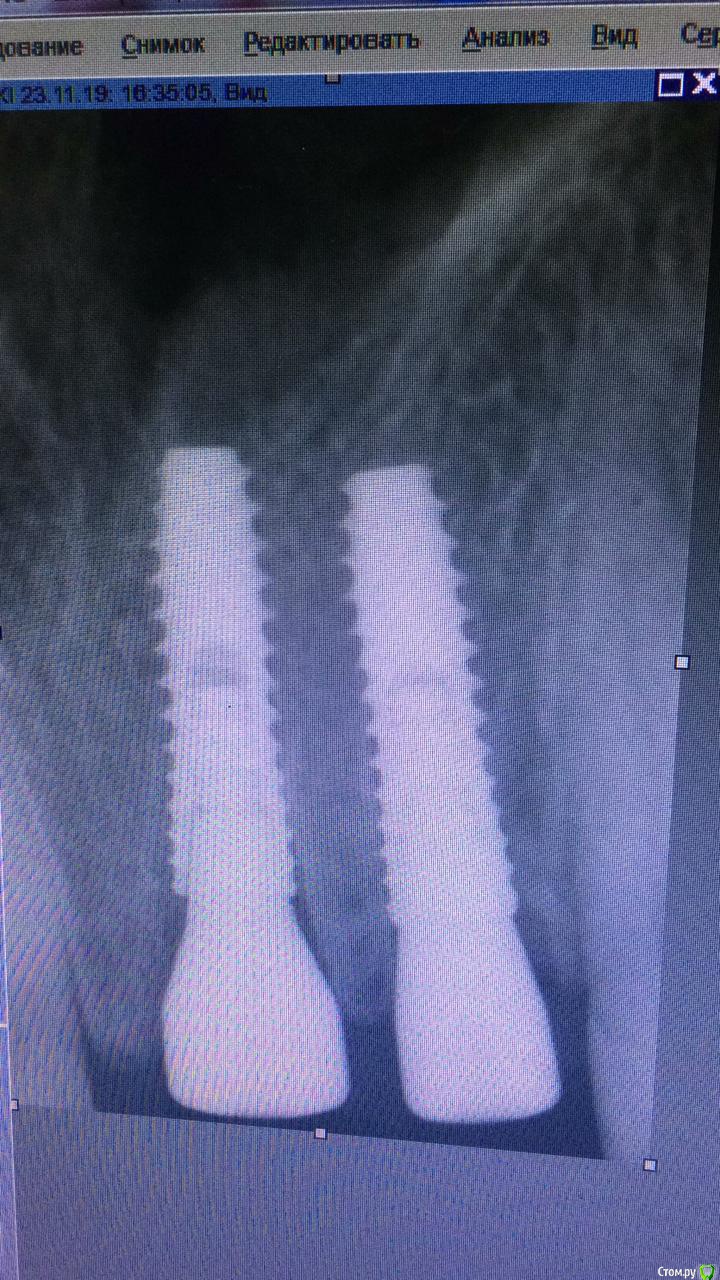

жулля Опубликовано 4 февраля, 2020 Поделиться Опубликовано 4 февраля, 2020 Добрый вечер! 23.11.19г. мне сделали одномоментную имплантацию двух передних зубов системой Имплантиум. и все 2 месяца у меня ощущения дискомфорта , то легкой боли при нажатии на десну, постоянно какие то ощущения. Я чувствую это место. ВРач говорит, что все хорошо. Очень переживаю за приживаемость, так почти везде пишут, что ничего не должно болеть. Языком надавливать сзади тоже чувствительность есть. Что посоветуете? Ссылка на комментарий

Irouil Опубликовано 4 февраля, 2020 Поделиться Опубликовано 4 февраля, 2020 Судя по всему, одна коронка недоприкручена, это может приводить к ее микроподвижности, попаданию пищи под десну. Ничего криминального, но, учитывая тот факт, что коронки связаны, я бы попробовал снять их и после проверки прикрутить заново. Но ситуация пограничная, сейчас период самый ненадёжный для механического воздействия на имплантаты, поэтому если в полости рта при осмотре доктор не видит повода для беспокойства, то, возможно, более рационально подождать ещё месяц-полтора, а пока в Вашу задачу будет входить идеальная гигиена вокруг имплантата с ежедневным использованием ирригатора Ссылка на комментарий

red_butler Опубликовано 5 февраля, 2020 Поделиться Опубликовано 5 февраля, 2020 + 1 открутить коронки, судя по снимкам формирователь десны упирался в край лунки, возможно и коронка/ки упираются, и лучше абатменты заменить на пластиковые. По Кт посмотрим взаимоотношение импланта и дна носа Ссылка на комментарий

red_butler Опубликовано 5 февраля, 2020 Поделиться Опубликовано 5 февраля, 2020 У меня не было формирователя десны. Было удаление, установка импланта и сразу коронокНа одном из снимков имплантаты с Формирователями Ссылка на комментарий

жулля Опубликовано 5 февраля, 2020 Автор Поделиться Опубликовано 5 февраля, 2020 На одном из снимков имплантаты с Формирователямиможет быть это самый первый снимок, ортопед опаздывал) Ссылка на комментарий